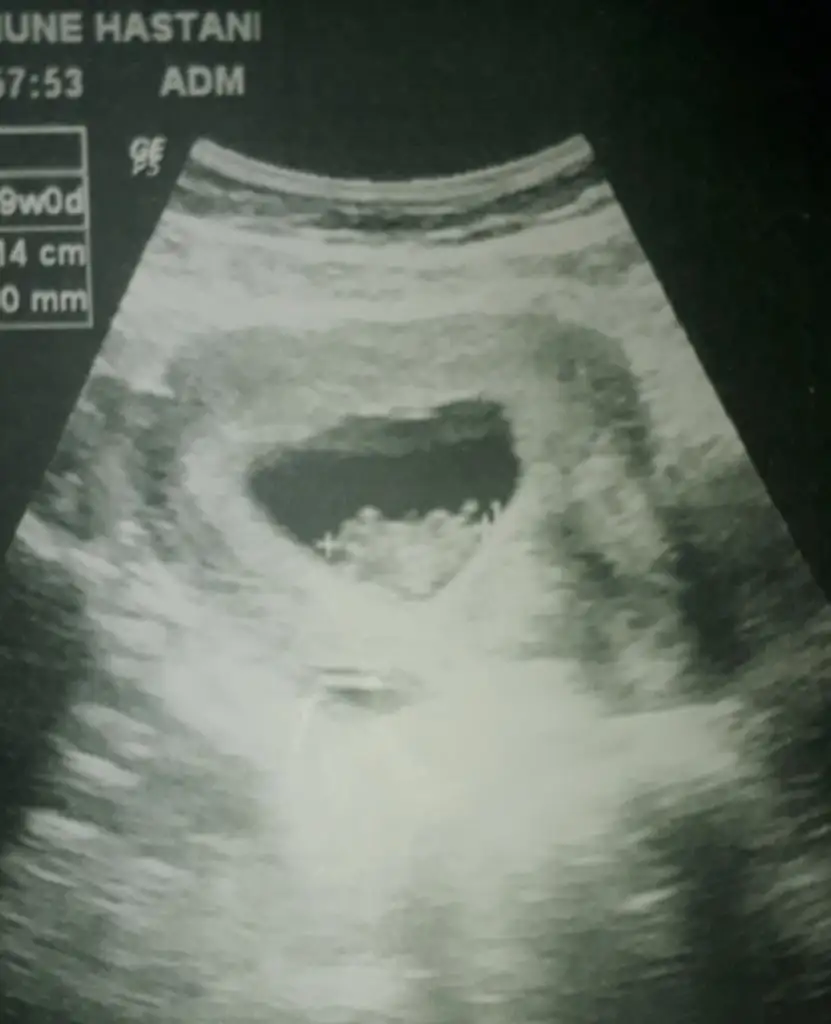

Onlar yok malesef 5+2 var 1 2 sayfa önce paylaşmıştım 9 hafta olan da bugün çekildi6+ olmalı kese için yada 11 hafta 12 hafta nub için paylaşın

ÖgrendinizmiTabi önce sağlık ama oğlu var bu kız olsun çok istiyor inşallah doğrudur tahmininiz çok teşekkürler

O haftaya gelince paylaşcam inşallahYinede siz 11 yada 11 hafta nub için paylaşın